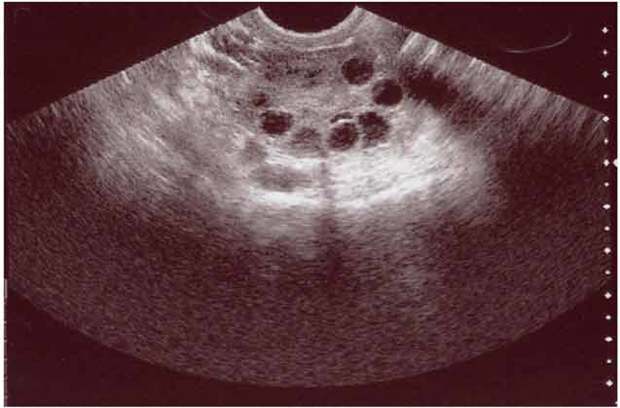

این متخصص زنان و زایمان درباره روش‌های تشخیص این عارضه گفت: تشخیص فیبروم با معاینه و سونوگرافی یا ام‌آرآی صورت می‌گیرد؛ همچنین فیبروم ممکن است در دوران حاملگی مشاهده شود، هرچند بسیار به ندرت باعث پیامدهای نامطلوب می‌شود. گرگین در خصوص گزینه‌های درمانی فیبروم گفت:‌ روش‌های درمانی فیبروم شامل درمان انتظاری توام با نظارت، درمان دارویی و درمان‌های جراحی به صورت برداشتن میوم به‌روش جراحی لاپاراسکوپی یا هیستروسکوپی یا جراحی باز است؛ در عین حال میزان عود فیبروم در 5 سال پس از جراحی ۱۱ درصد است و در نهایت پیگیری و سونوگرافی روش مناسبی برای بررسی عود فیبروم است.